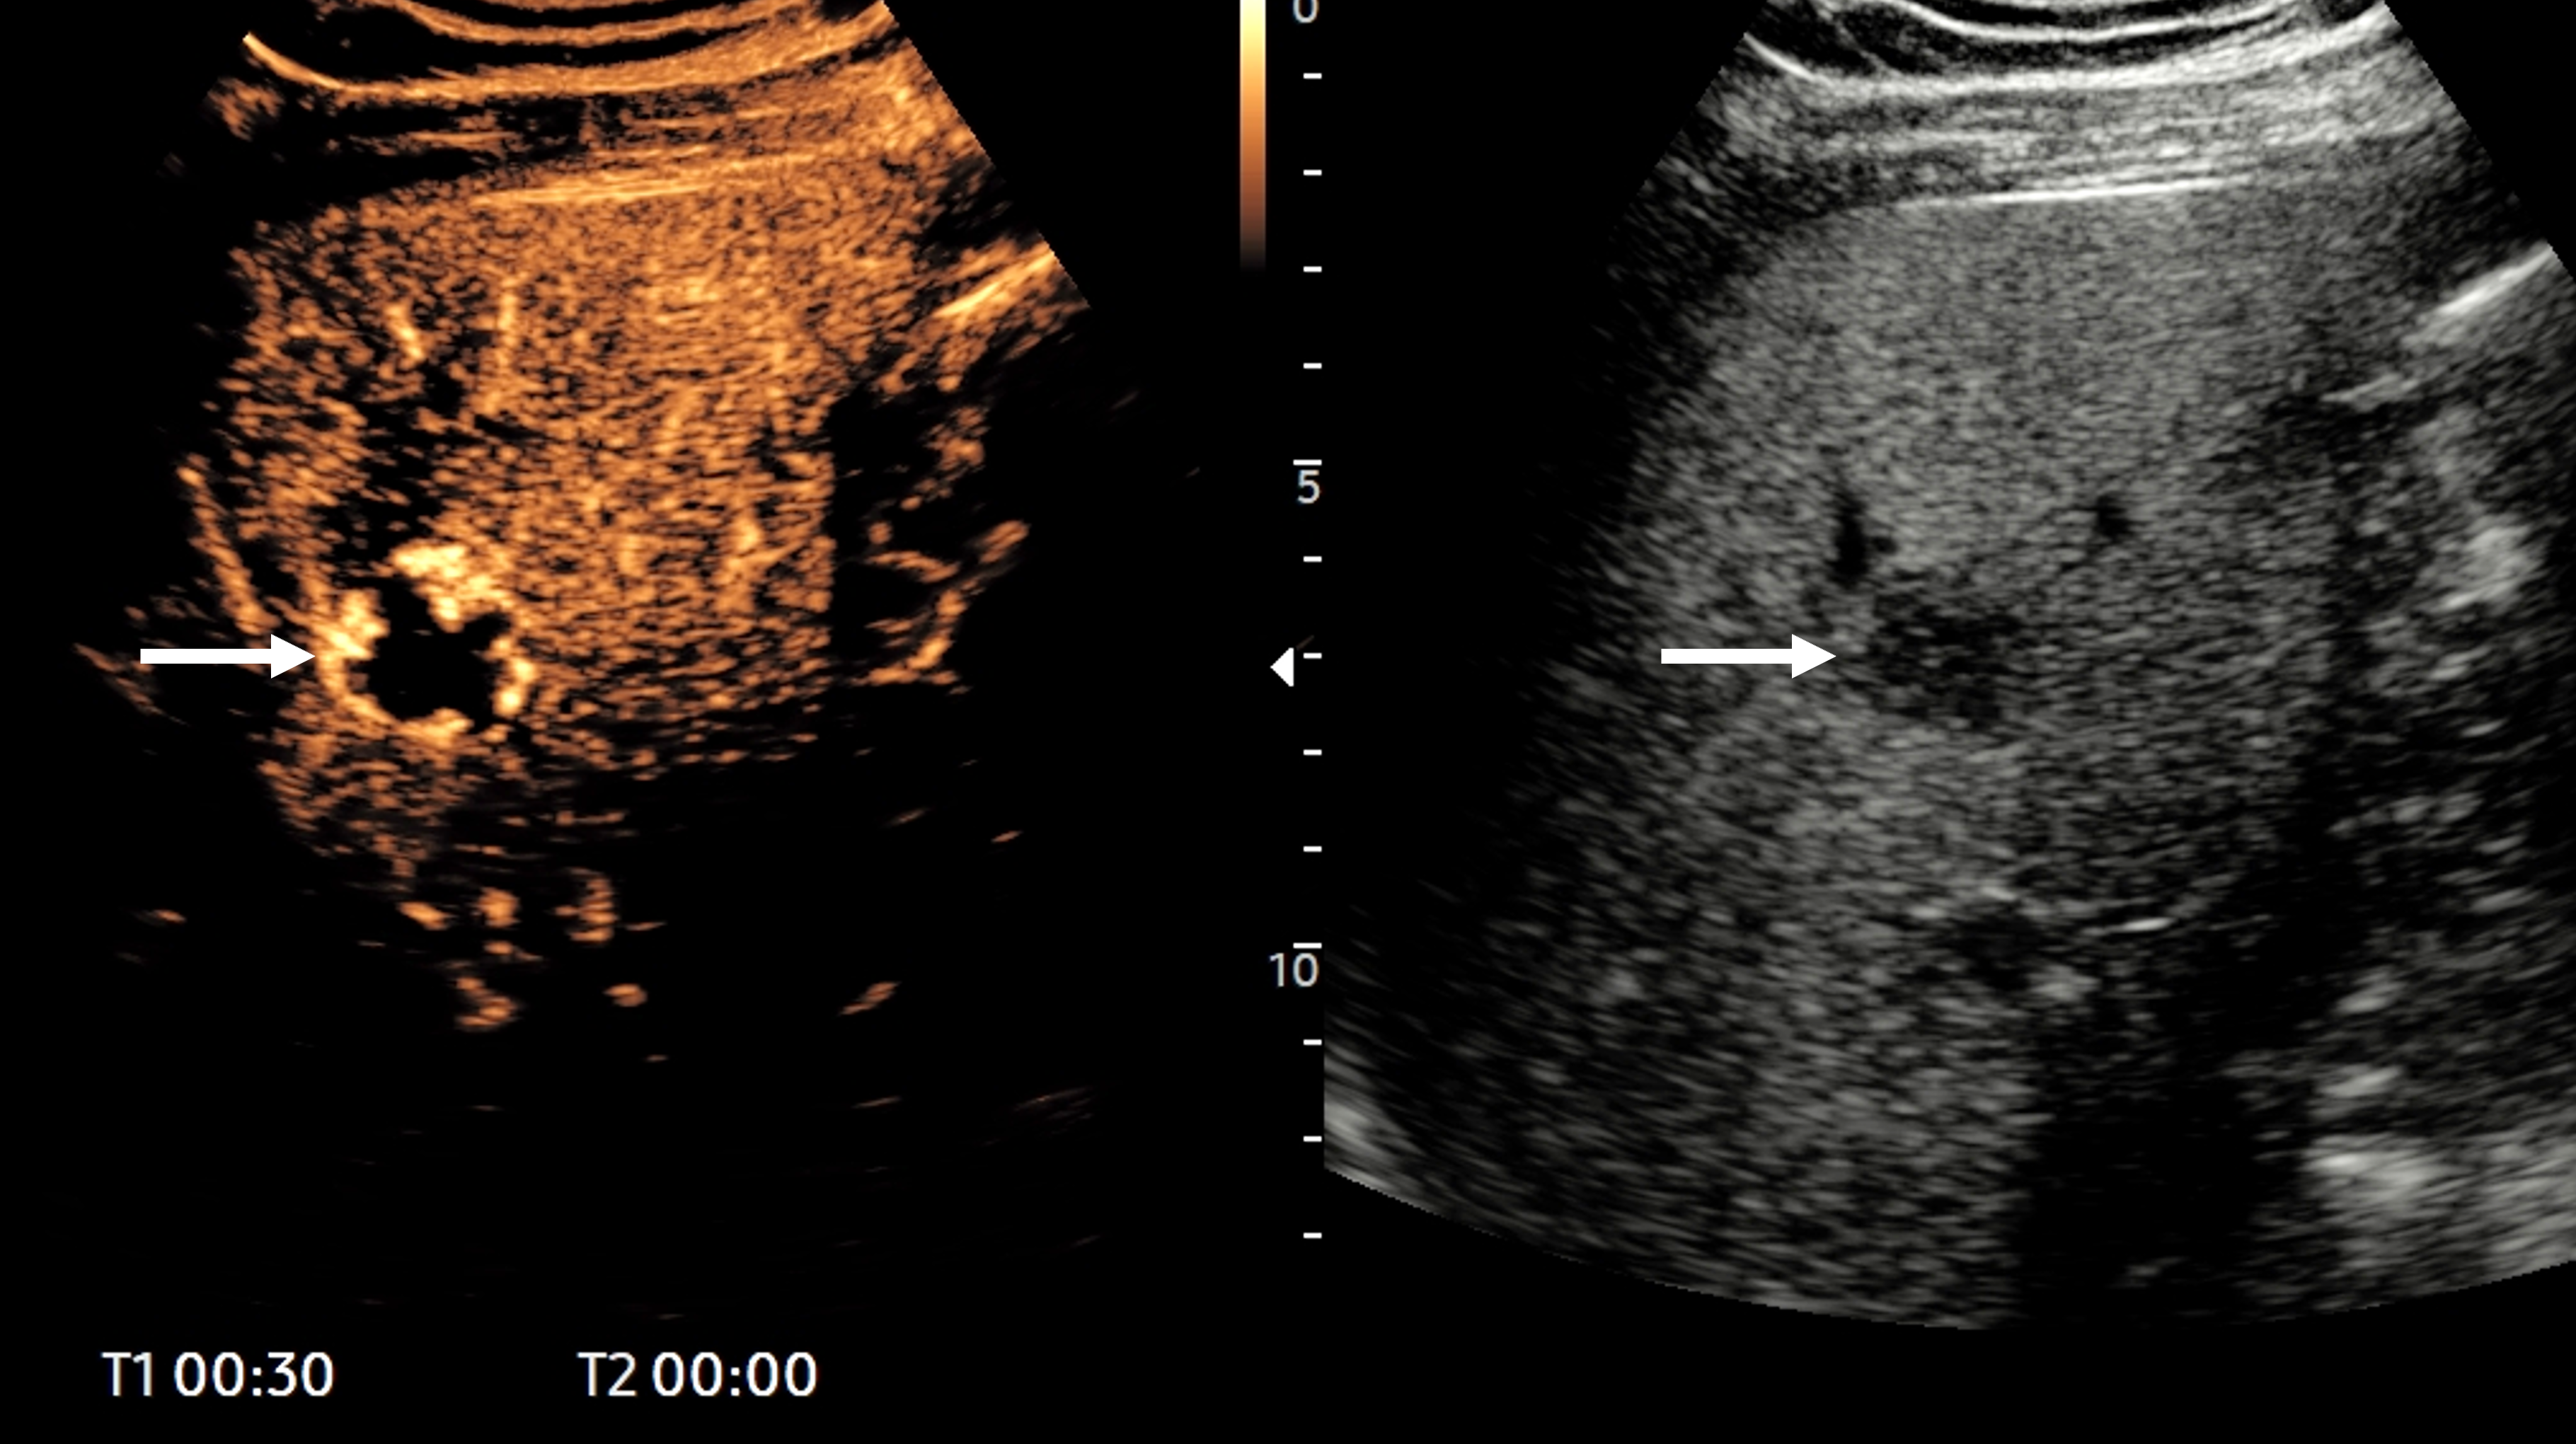

The device will be integrated into select GE HealthCare Logiq ultrasound systems and will provide access to advanced AI-supported 3D imaging capabilities, the company said. Piur tUS inside uses proprietary sensor technology to provide diagnostic tomographic 3D imaging, such as automatic reconstruction of sagittal, transverse, and coronal views. Clinicians can attach the compact Piur Sensor during 3D scans and remove it for routine 2D use, according to the firm.